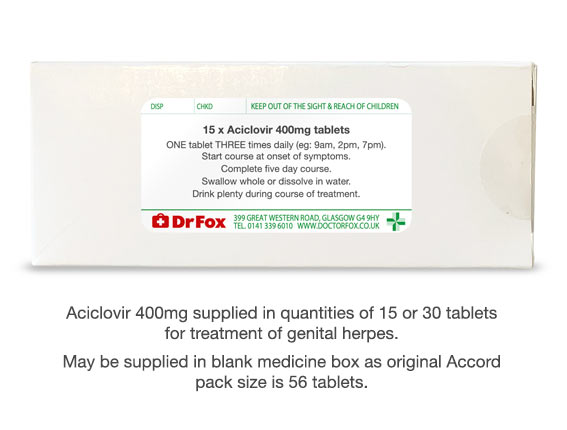

Aciclovir ACV, also known as acyclovir, 3 is an antiviral medication. Common side effects include nausea and diarrhea. |

Aciclovir also known as Acyclovir is one of the most commonly used antiviral medications to treat herpes simplex viruses, including genital herpes herpes simplex strain 2, HSV-2 and cold sores herpes simplex strain 1, HSV It also treats varicella zoster virus VZV, herpes zoster, which causes chickenpox and shingles. |

If you are suffering from herpes virus infections, Acyclovir can help. Visit with a doctor on your smartphone or computer. |